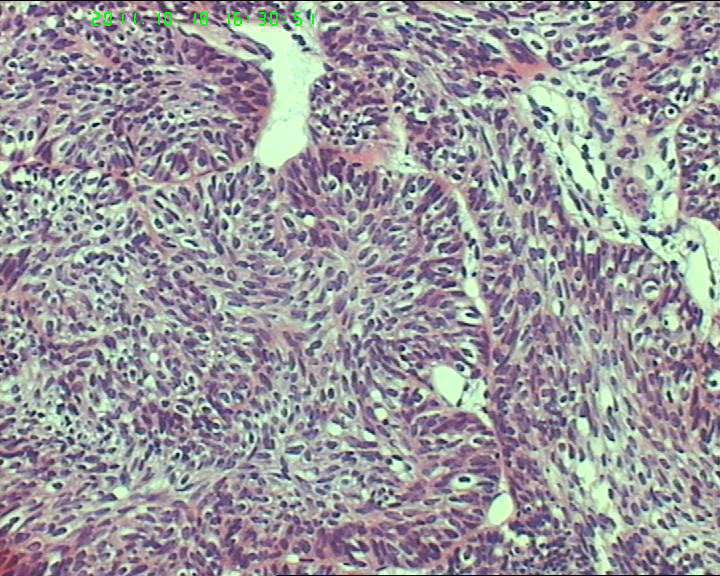

70岁女性体检发现膀胱肿物,是癌吗?

膀胱后壁一2*1cm大小肿物